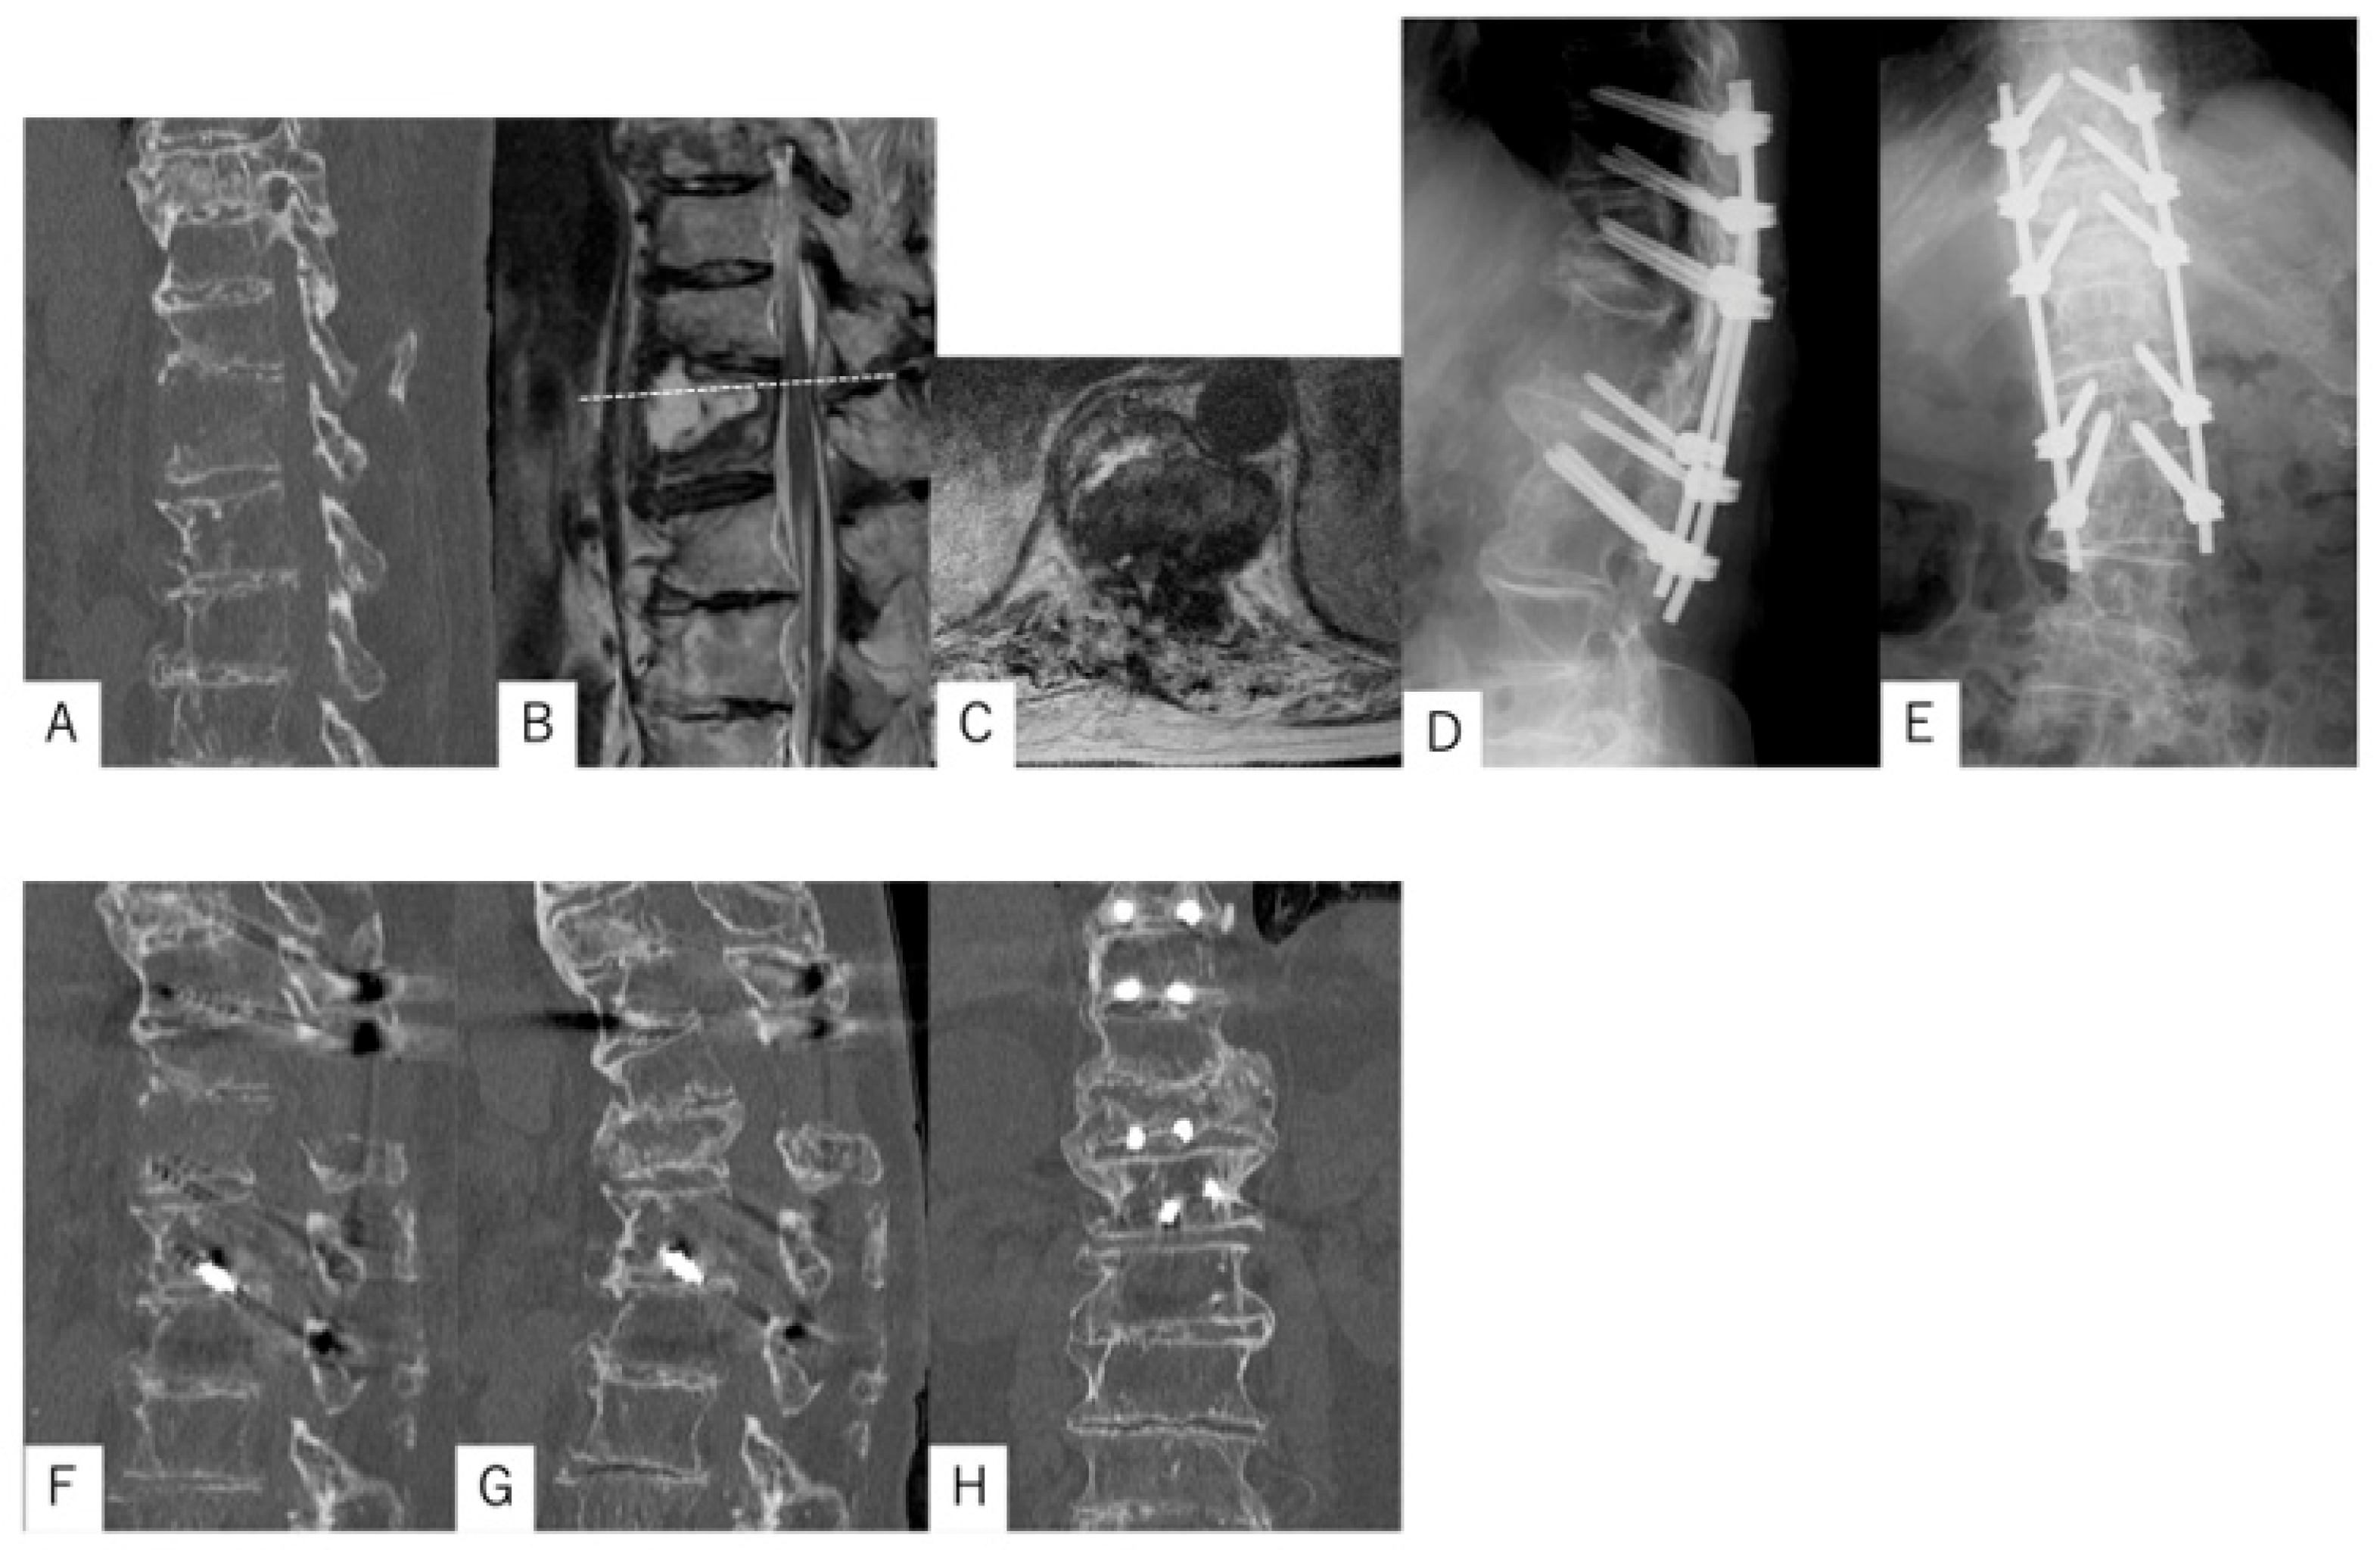

3.1. Case Presentation 1

3.2. Case Presentation 2